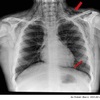

5

Perfectly

6

Q

Técnicas de imagen para ver Enfisema-EPOC-EI

A

TC